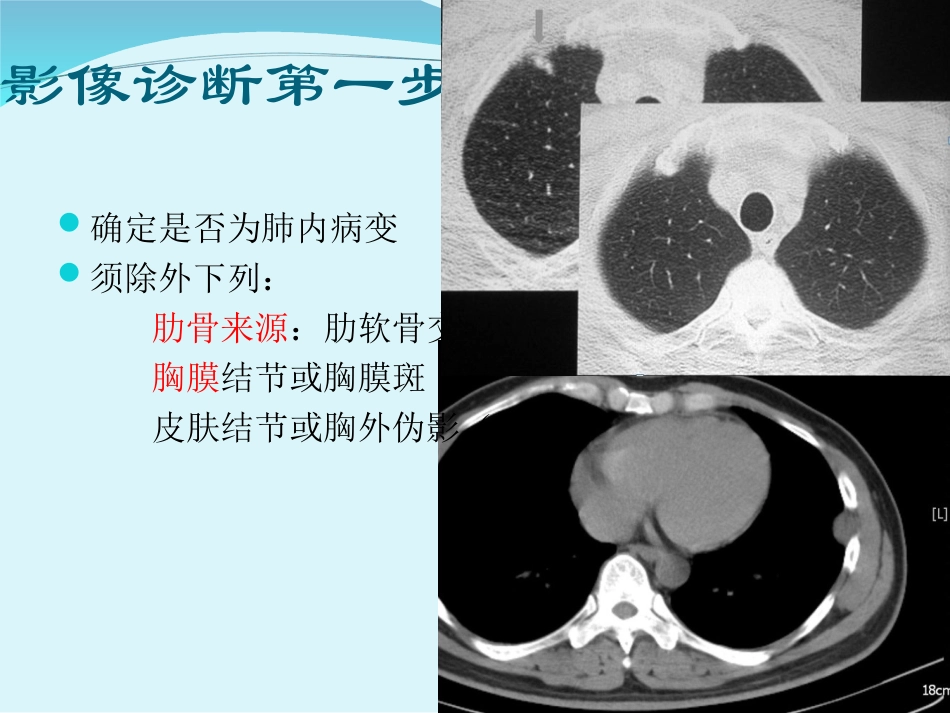

温医大附二医定义两侧肺实质内发现单个球形或类球形密度增高影不伴有肺门或纵隔淋巴结肿大,肺不张,肺炎长径不大于3厘米有足以测量其直径的、有一定锐利度的边缘病变内可有钙化或空洞(不包括占据病变大部分的空洞者)肺内可见到其它病变。影像诊断第一步确定是否为肺内病变须除外下列:肋骨来源:肋软骨交界处的增生,骨折后的骨痂胸膜结节或胸膜斑皮肤结节或胸外伪影(胸片)SPN的可能诊断肿瘤性炎性先天性其它肿瘤性支气管肺癌转移瘤原发肺淋巴瘤不典型腺瘤样增生(AAH)错构瘤结缔组织和神经肿瘤:脂肪瘤,纤维瘤,软骨瘤,神经纤维瘤,肉瘤。炎性感染性:肉芽肿:结核,组织胞浆菌,隐球菌,酵母菌,球孢子菌球形肺炎:急性或慢性肺脓肿包囊虫病非感染性:类风湿性关节炎韦格纳肉芽肿淋巴瘤样肉芽肿结节病类脂性肺炎白塞氏病先天性动静脉畸形肺隔离症肺囊肿支气管闭锁并粘液嵌塞其他多方面原因的机化性肺炎肺梗塞球形肺不张肺内淋巴结粘液嵌塞肺动脉瘤或静脉曲张SPN的可能诊断恶性肿瘤:原发或转移炎性肉芽肿:结核或真菌良性肿瘤:最常见—错构瘤约占95%以上!临床因素年龄因素<30岁:通常为良性,但需连续追随观察两年30-39岁:大多数良性,恶性不罕见>40岁:恶性相当常见吸烟史结节的CT分析形态学表现密度改变增大速度结节的形态学表现1.大小2.位置3.边缘4.胸膜凹陷征5.支气管充气证和空泡征6.血管集中征7.空洞1、结节的大小0.5-1.0cm67.5%良性1.0-2.0cm良恶性发生率相等≥2cm85%为恶性结节2、位置原发性肺癌上叶常见,尤其是右肺,前段比后段常见转移瘤更倾向于在两下叶的胸膜下,60%直接贴胸膜或胸膜下,25%外1/3带肺内淋巴结边缘光滑的外围结节中占17%3、边缘恶性结节的边缘不规则、分叶状、脐凹征、毛刺状良性结节边缘光滑锐利的圆形或椭圆形结节病理基础分叶状边缘肿瘤的结节状过度增生所致毛刺影结节中的促结缔组织增生反应产生向周围肺野内放射的纤维性线条肿瘤直接向邻近支气管血管鞘内浸润或局部淋巴管扩张所致4、胸膜凹陷征定义位于肺周围的孤立性结节和邻近的胸膜之间可见从结节外缘向胸膜移行的三角形或放射状线条影绝大多数见于腺癌和细支气管肺泡癌,少见于鳞癌和类癌,转移瘤极少见于63.3-78.6%的肺癌结节良性结节占27%肺腺癌支气管充气证定义支气管影直接进入结节或在结节内包含有支气管影,呈上、下层连续的长条状或分子状小透亮影恶性结节:发生率不同28.7-65%腺癌为主良性结节:局限性机化性肺炎常见5、空泡征定义:结节内1-2mm的点状低密度透亮影见于50%的细支气管肺泡癌病例中偶可见于良性结节中6、血管集中征(滋养血管征)定义:与结节相伴行的一条或几条小血管受病变的牵拉或侵犯而向结节方向集中肿瘤多见,三维重建时能更好显示与滋养血管有比较直接关系转移瘤、肺梗死和动静脉畸形7、空洞定义结节内有较大而无管状形态的低密度透亮影直径大于5mm大于结节所在位置相应支气管管径的2倍与上下层面支气管不相连的圆形或类圆形低密度透亮影肺结核肺脓肿空洞病理——为结节内有坏死液化并已排出薄壁且内壁光滑的几乎都是良性的厚壁时则不一定,即使呈内壁不光滑也不是恶性结节的特征性改变壁厚≤4mm倾向于良性≥15mm倾向于恶性结节的密度1.钙化2.日晕征和磨玻璃结节3.脂肪4.液体5.增强表现1、钙化普通胸片中孤立肺结节内出现钙化是诊断良性结节的比较可靠的征象少数肺癌结节中可发现钙化,胸片上肺癌钙化的检出率约1%钙化的形态良性结节的形态同心圆性层状、靶心状、弥漫或爆米花状钙化恶性结节的钙化针尖状或偏心位置结核瘤的钙化往往面积较大,所占面积常大于10%。薄层扫描时可见到钙化时其CT值约在400Hu以上2、日晕征在软组织密度的结节周围出现环状的磨玻璃影首先由Kuhlman提出是诊断早期侵入性曲霉菌有价值的征象也可见于伴有咳血的结核瘤、经支气管活检后的肺结节等结节出血或周围水肿的CT表现2、磨玻璃结节(GGN)定义:肺内边缘清楚的圆形或类圆...